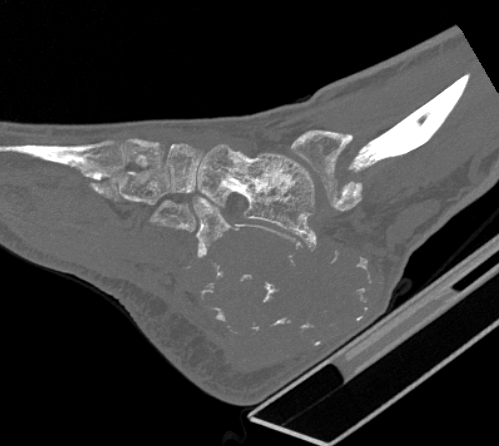

Osteoid osteoma

Especially common in hindfoot

Difficult to diagnose on x-ray - CT / MRI / bone scan

CT guided RF ablation